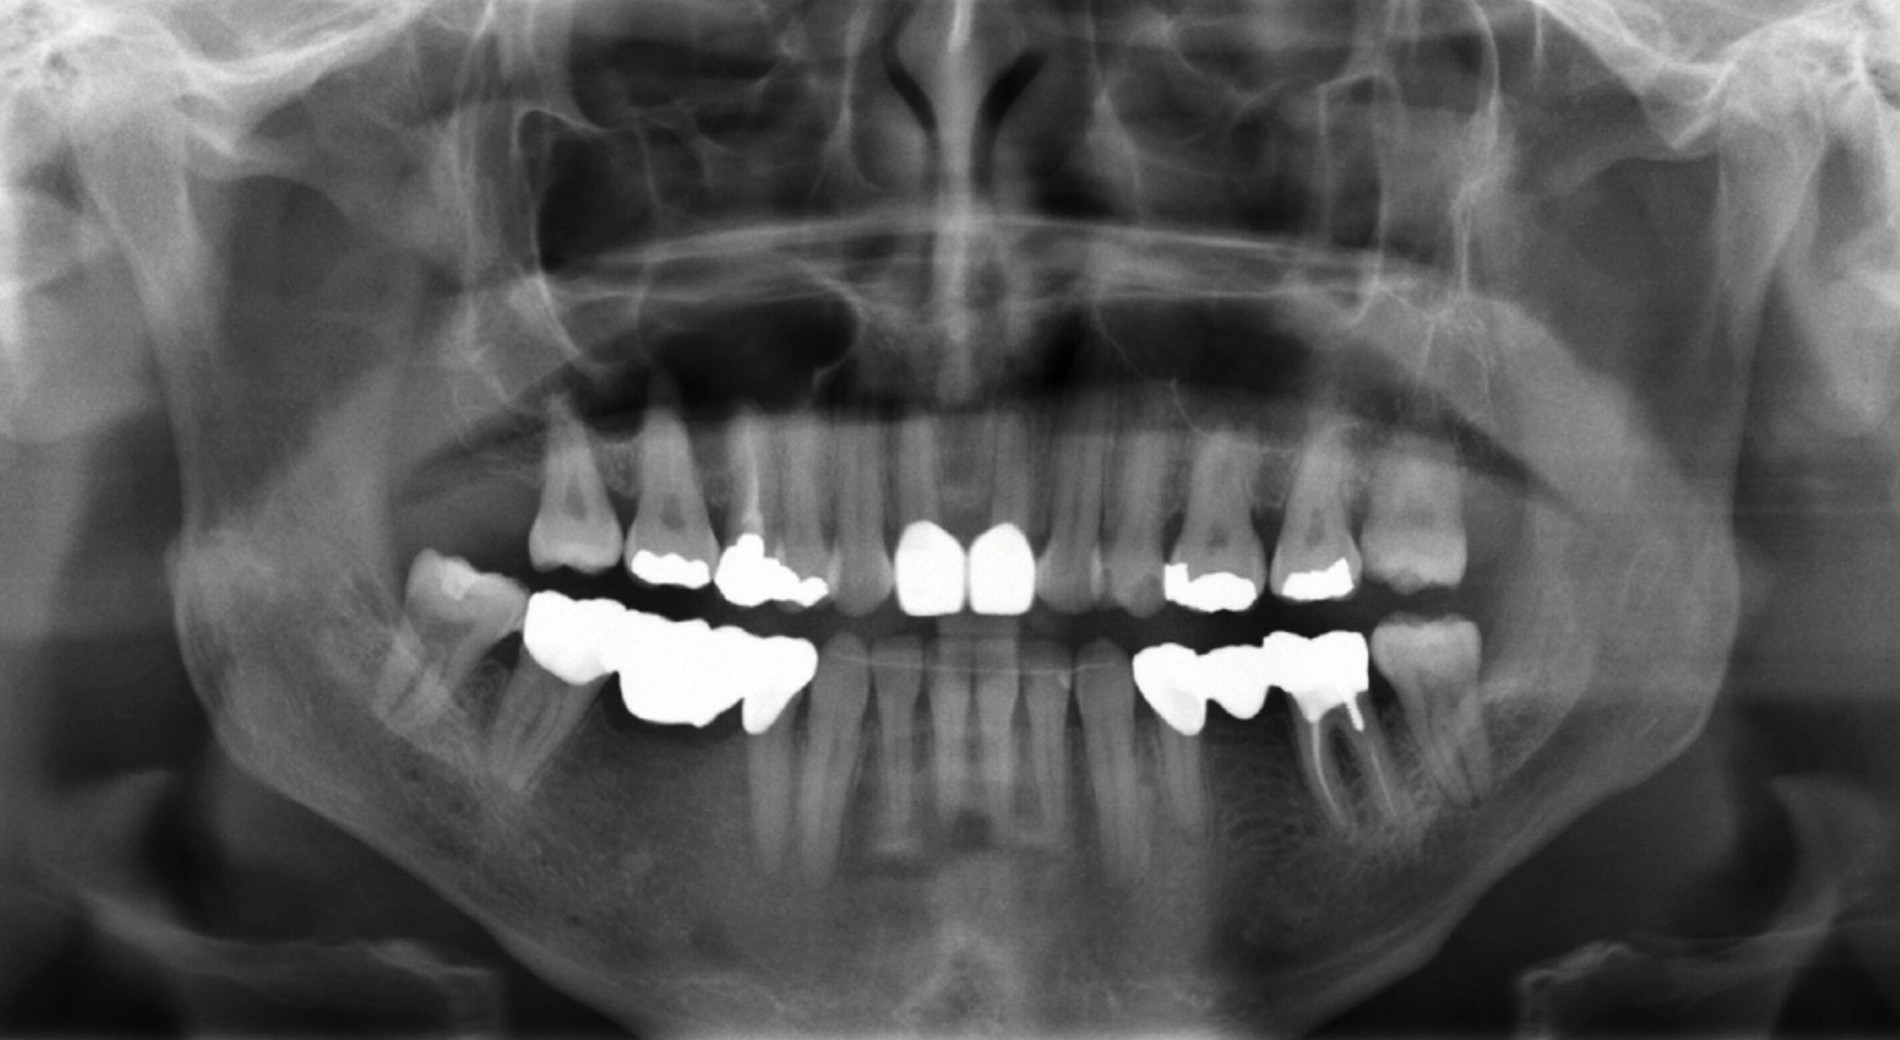

Die Auswertung der Fernröntgenseitenaufnahme ergab eine orthognathe Maxilla (SNA: 80,7°) und eine prognathe Mandibula (SNB: 90°) bei Vorliegen eines dolichofazialen Wachstumsmusters (Abbildung 4). Zudem deuteten die Ergebnisse auf eine mesiale basale Diskrepanz hin (ANB: -9,2° und WITS: -8,2 mm). Die Oberkieferfrontzähne zeigten eine orthoaxiale Stellung, während die Unterkieferfrontzähne einen ausgeprägten lingualen Kippstand aufwiesen. Die kephalometrischen und die klinischen Befunde deuteten somit auf ein Long-Face-Syndrom hin.

Aufgrund einer hohen Kariesanfälligkeit und einer klinisch floriden Parodontitis waren bereits mehrere Zähne des Patienten extrahiert worden, darunter 16, 11, 25, 38, 35, 45 und 46. Die mesiale Kippung und Aufwanderung der angrenzenden Zähne ließ vermuten, dass der Zahnverlust zeitlich weiter zurücklag. Aufgrund der reduzierten Langzeitprognose des Zahnes 11 entschieden wir uns gemeinsam mit dem Patienten für eine Ausgleichsextraktion des Frontzahns.